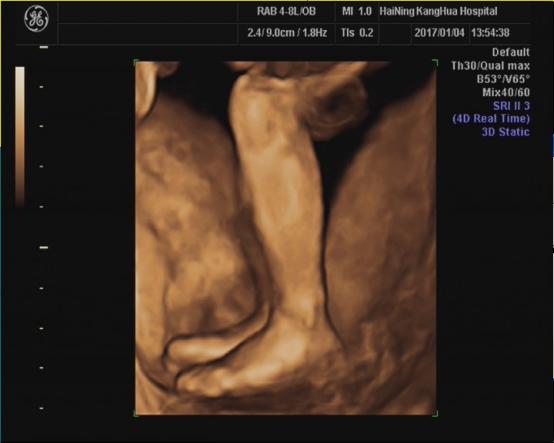

海宁康华医院“胎儿三维彩超检查”,为您创造“透视”条件!

胎儿三维超声检查最佳时间:

22—24周(备注:双胎不做三维超声检查)